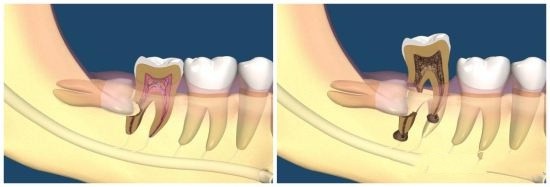

為了長出來,智齒只能“自私”地頂壞前面的牙齒。

這也就是智齒會引起牙疼、牙齦發炎等問題的原因。

但凡位置不正,別管屬於專業術語中的哪一種型別,都存在萌出頂壞牙齒的風險,建議拔除。

尤其是那些“蠢蠢欲動”的智齒,已經引起了牙疼、牙齦發炎等情況,哪怕吃點消炎藥將炎症又下去了,後面也會反覆發作,並且一次比一次疼,一次比一次嚴重。